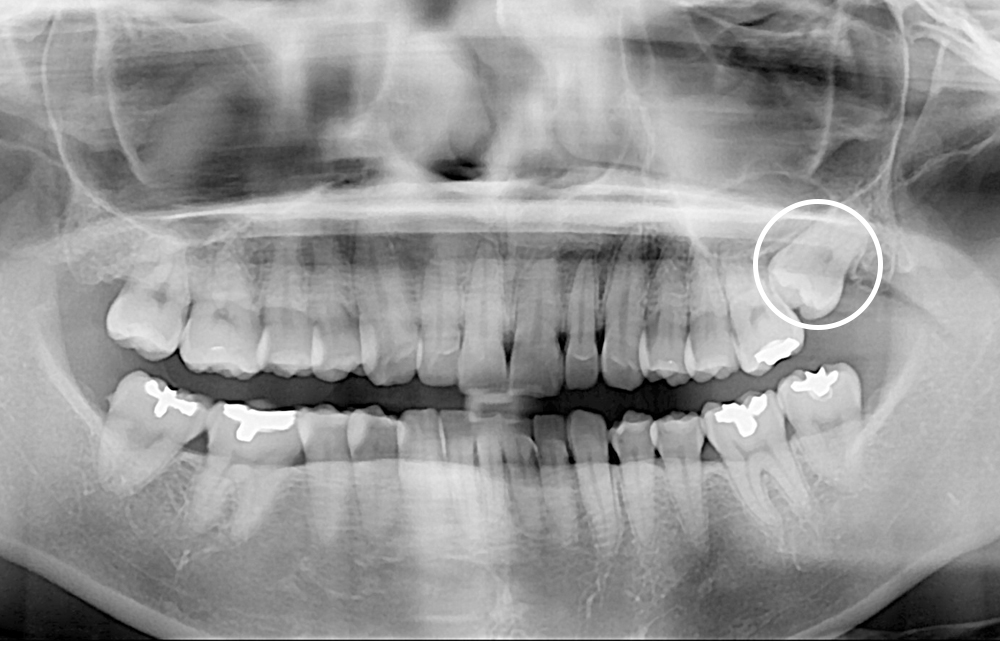

[사랑니] 매복 사랑니 발치

치료전 : 2020-01-14

세종치과는 구강악안면외과학 박사이신 원장님이 발치하는 치과입니다.